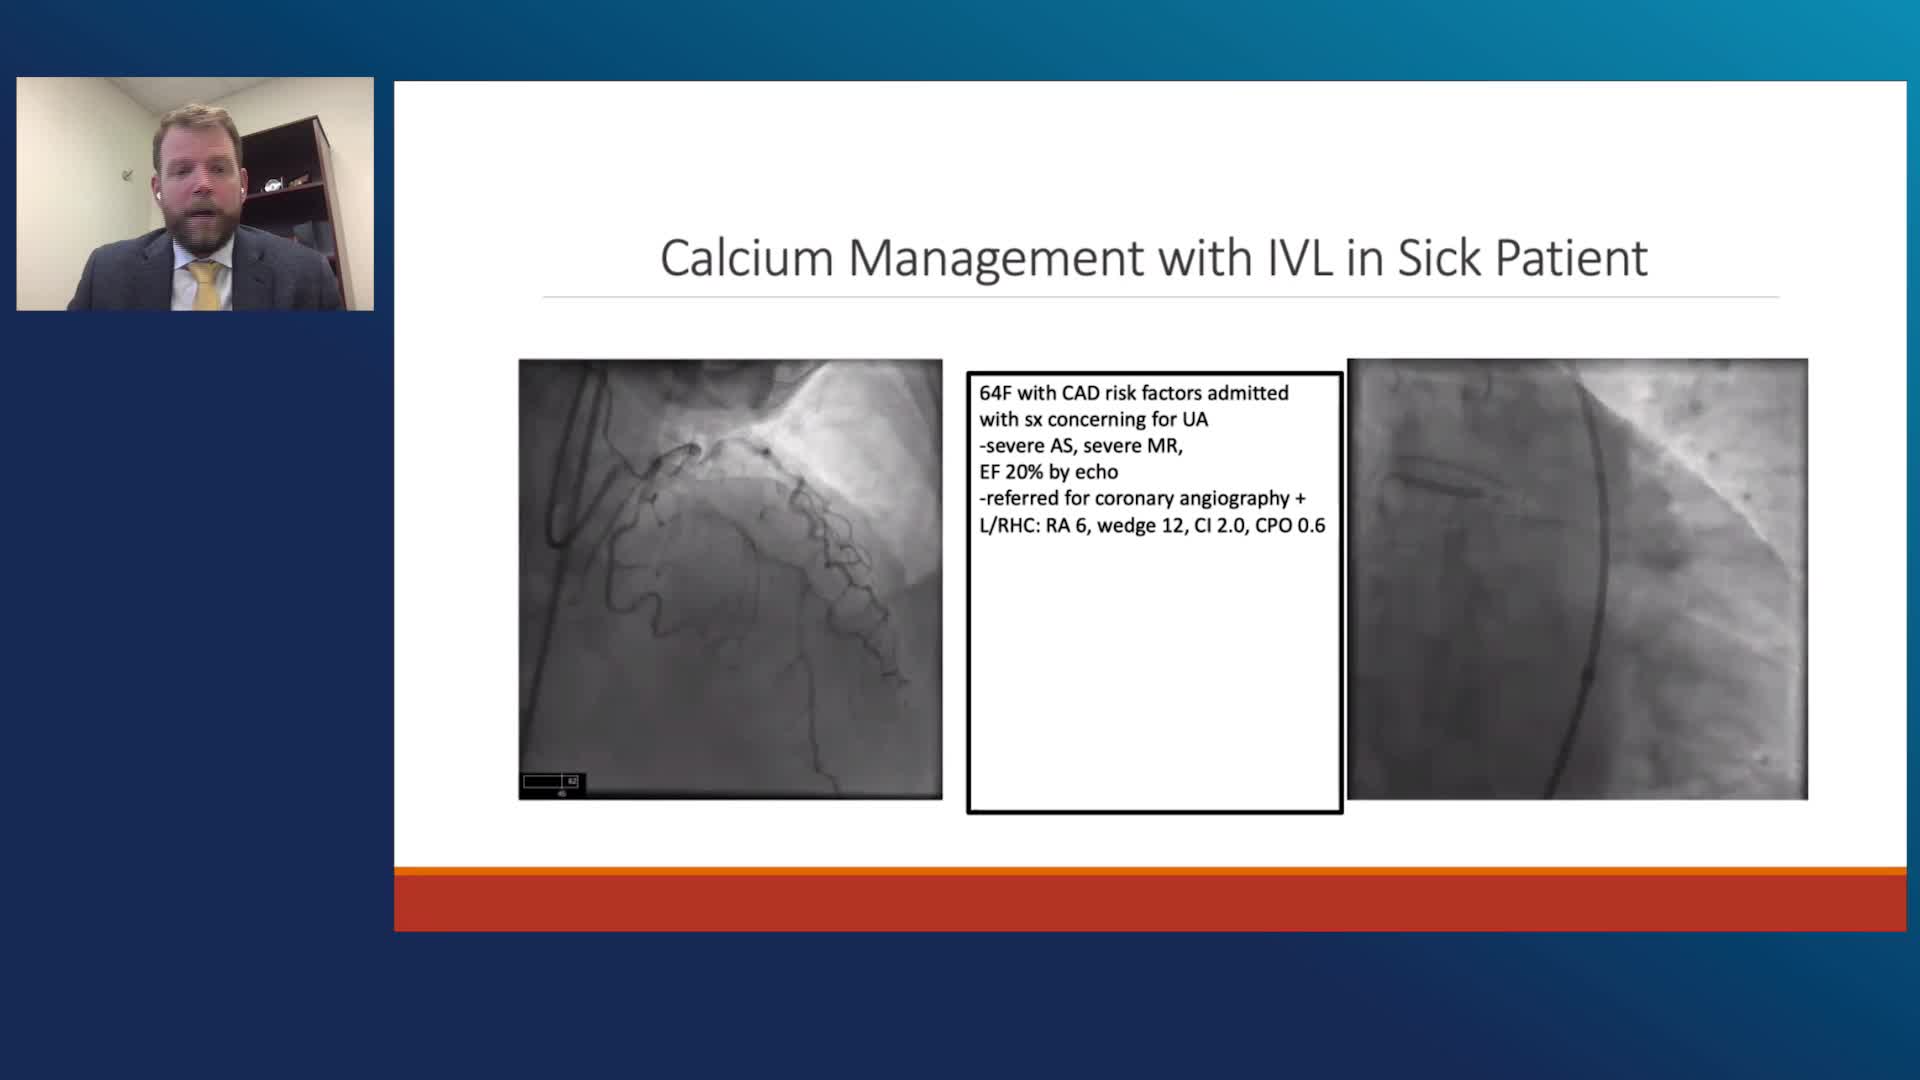

Shockwave IVL Coronary Real-World Cases, Outcomes & Algorithms: An InCathLab Webinar

Shockwave IVL